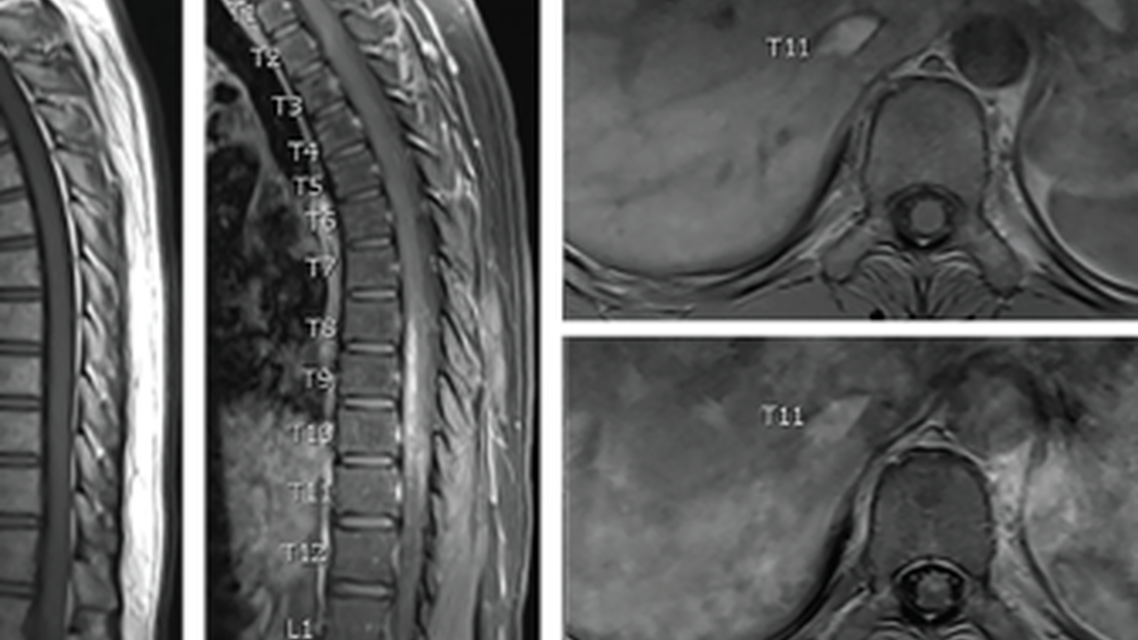

The findings of Mr. M’s initial laboratory evaluation were notable for mild eosinophilia (absolute eosinophil count [AEC] 550) and elevated C-reactive protein (CRP) of 0.90 (reference value=0-0.49). Before catheterization, urinalysis was notable for mild hematuria (10 red blood cells (RBCs) / high-power field (HPF); reference value=0.3 RBCs/HPF). Whole spine MRI showed central spinal cord enhancement from T1 through the conus medullaris with mild cord expansion and profound anterior cord enhancement from T8 through T11 with nerve root enhancement in the cauda equina (Figures 1 and 2).